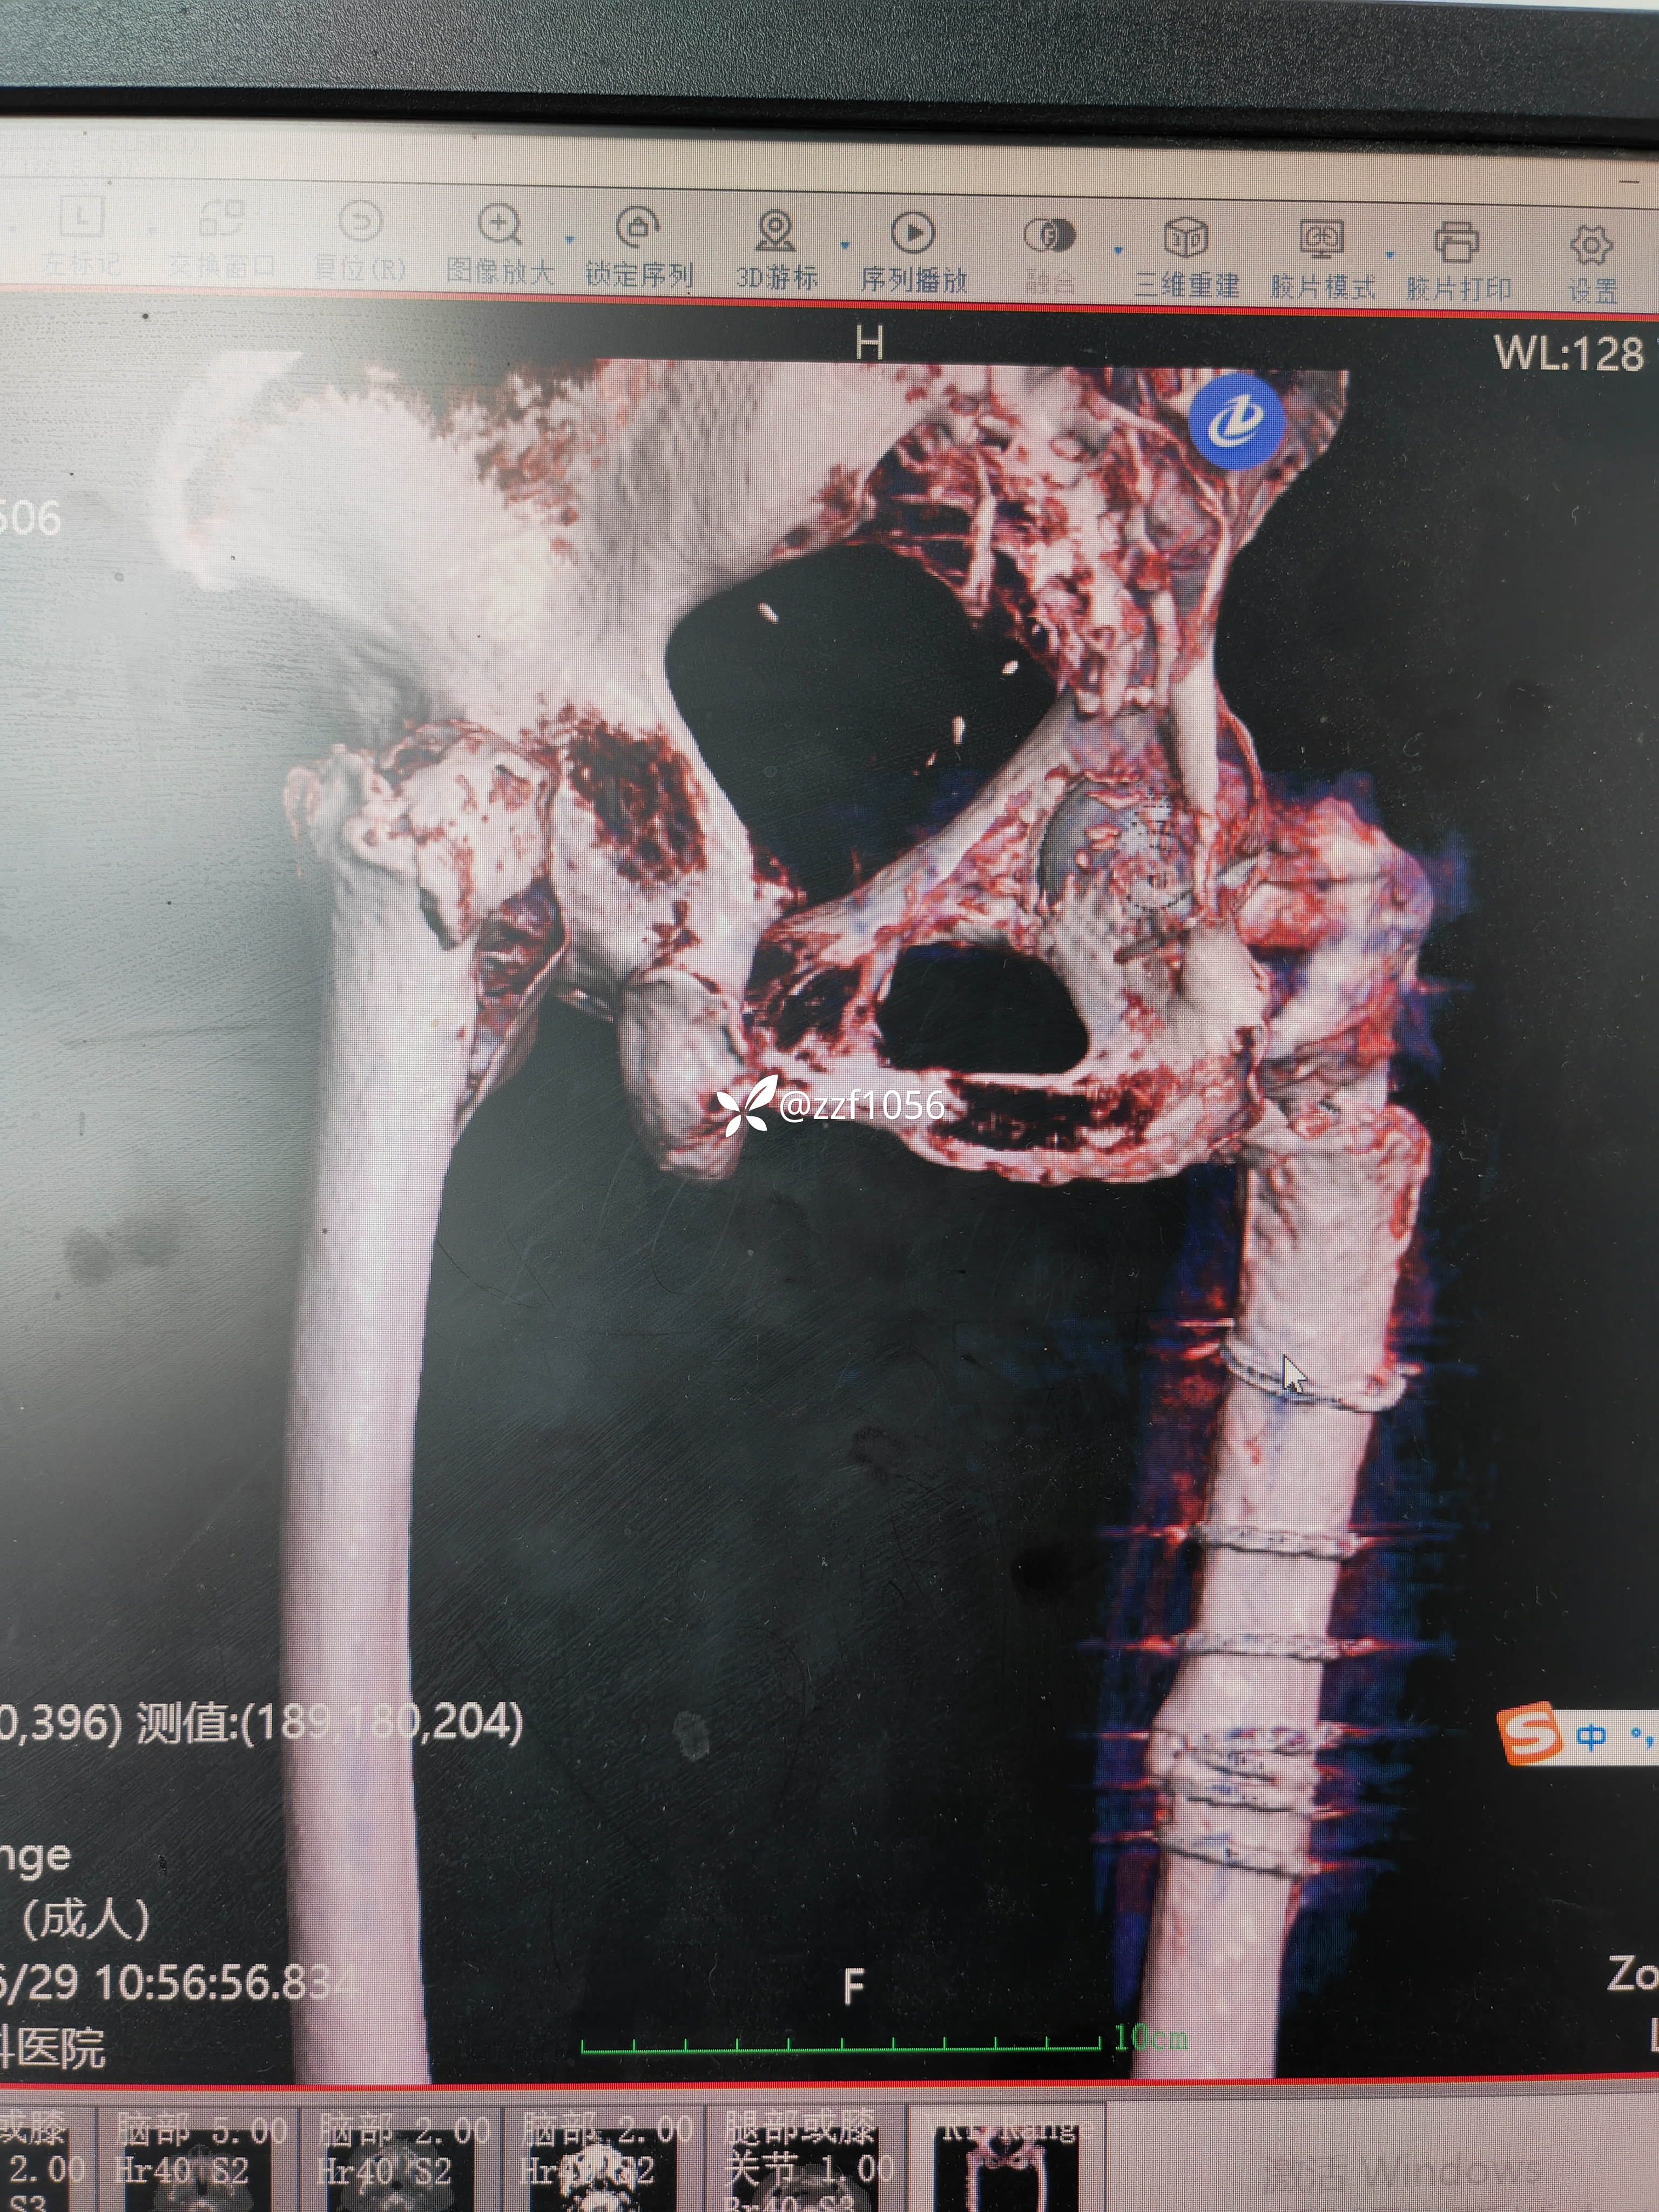

术中去除内固定顺利,使用瓦格纳柄,术中出现插曲,出血量多和干部骨折,多处捆扎,全髋改半髋下台,😰虐心,懂得都懂

行走三个月康复良好,奈何再次摔伤,导致左侧转子间再骨折,A2.3型